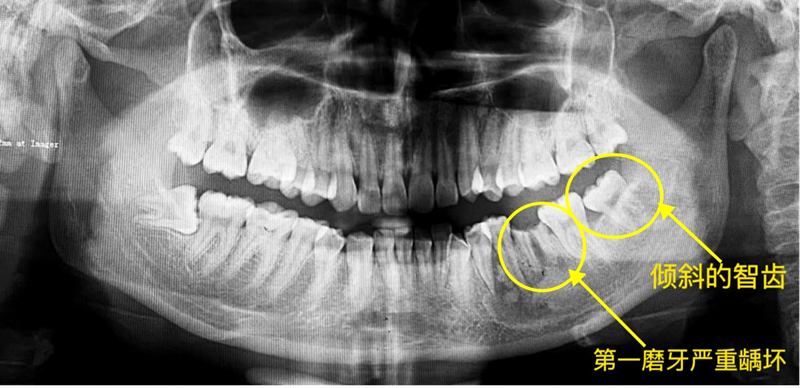

以下为口腔门诊部治疗案例展示:患者姚女士左下第一磨牙因为严重龋齿而拔除,左下智齿倾斜,但牙体无龋坏,牙周情况良好,加上患者牙齿不齐,有矫正牙齿的意愿,经过医生充分评估和沟通后开始了正畸治疗。经过正畸治疗,患者不仅左下智齿逐渐排齐,恢复正常咬合,原来磨牙缺失造成的间隙得以关闭,还收获了整齐的牙列。

(患者治疗前牙片)